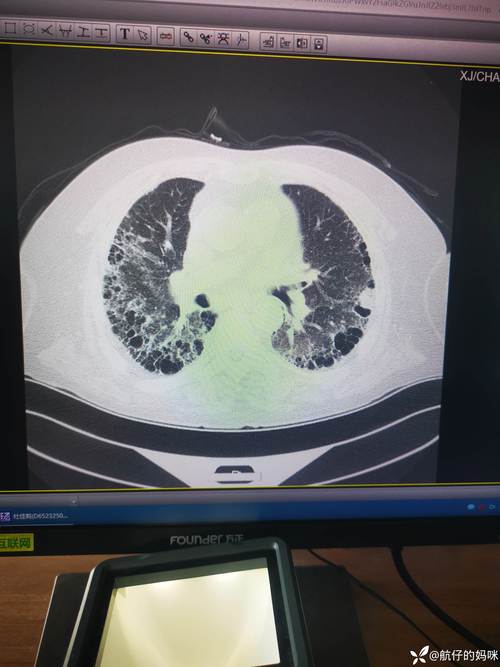

- 疾病性质:肺纤维化不是一种单一的疾病,而是一大类以肺组织进行性纤维化、瘢痕化为特征的疾病,正常的肺泡(负责气体交换的微小囊泡)被“疤痕组织”(纤维组织)取代,导致肺部变硬、弹性变差。

- 间质性肺病:这是最核心的类型,指肺间质(肺泡和血管之间的区域)的病变,其中寻常型间质性肺炎 是最常见、最严重的纤维化类型。